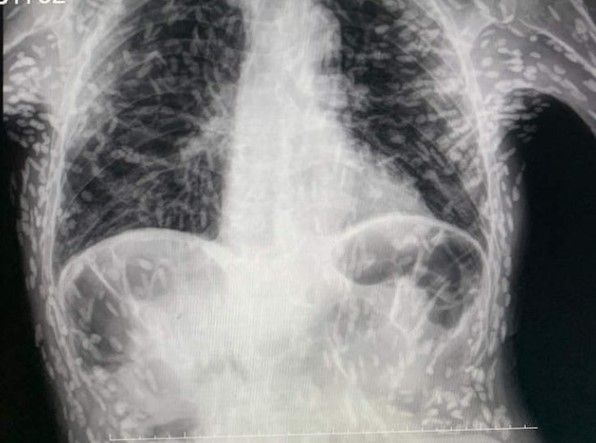

一名巴西醫師在4月中上傳一張病患胸部X光照到網路上,只見照片中病患的肺部布滿「白色點點」,畫面相當嚇人。該名病患表示自己已持續咳嗽2個月,經醫師檢查後發現是患囊蟲病(Cysticercosis,又稱囊尾幼蟲病),白色點點是病患體內感染的寄生蟲死亡後鈣化留下的囊腫。

德索薩指出,X光片中的白點是絛蟲幼蟲引起的囊腫,即絛蟲鈣化殘骸,就像皮膚下的腫塊。病人需進行MRI掃瞄,才能確認大腦囊腫的位置,若出現在大腦,就可能觸發頭痛、癲癇發作、失明,囊腫亦引致患者出現頭暈、腦積水等問題,未經及時治療隨時都可能喪命。

除了寄生蟲發育在頭部、脊髓或眼睛之外,患者其實並不需要治療,囊腫可能要數個月甚至數年才會形成,但絛蟲可能很快鈣化死亡。囊腫若積蓄在肺部,出現咳嗽及胸痛症狀,可透過手術或抗寄生蟲藥物移除;不過目前德索薩已刪除該篇貼文。